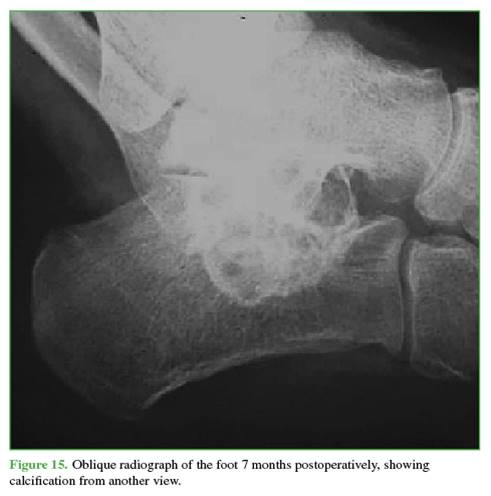

In successive clinical and radiological follow-ups, cyst ossification and pain resolution were confirmed (Figures 13-15). After more than two years of follow-up, the patient has not sought further medical consultation. Since ABC is known to have a recurrence risk, long-term monitoring should be maintained.